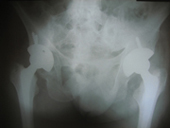

Arthriis of both hips pre op Arthriis of both hips post op Arthritis knee valgus deformity pre op Arthritis knee valgus deformity post op

Arthritis both knees varus deformity pre op Post op Total Knee Replacement Post op Total Knee Replacement